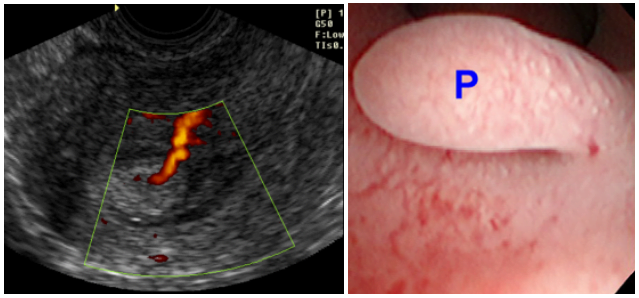

O pólipo endometrial também pode ser assintomático e regredir espontaneamente em até 30% dos casos, principalmente quando únicos e menores de 1 cm. Sem dúvida a ultrassonografia transvaginal auxiliará no diagnóstico e no acompanhamento (na fotografia abaixo e à esquerda, o pólipo endometrial está identificado pela imagem típica do vaso sanguíneo que o alimenta).

Quando indicado tratamento cirúrgico, a histeroscopia (na fotografia abaixo e à direita, o pólipo endometrial está representado pela letra “P”) é o método de escolha e pode ser realizada até mesmo em ambiente ambulatorial para pólipos pequenos. O tratamento dos pólipos endometriais maiores, contudo, requer internação hospitalar e abordagem em centro cirúrgico, com a devida anestesia.